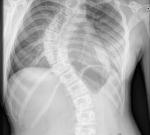

Менее чем за год неумолимая болезнь изогнула позвоночник девочки на 90°

Читать дальше

Двенадцатилетняя английская школьница с раннего детства была очень живым, подвижным ребенком. В школе она занималась спортом и танцами, а физкультура была одним из самых любимых ее предметов. Однако в прошлом году Эллен настиг тяжелый и довольно редкий недуг – в течение 10-ти месяцев ее позвоночник искривился почти под прямым углом. Теперь ей предстоит сложная операция, но девочка с нетерпением ждет ее, чтобы потом вновь вернуться к занятиям танцами.